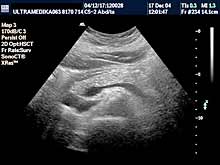

Pregledi abdomena

Standardni pregled podrazumeva pregled svih organa stomaka:

jetra, žučna kesa, žučni putevi, pankreas, slezina, bubrezi, limfne

žlezde,

cevasti organi, veliki krvni sudovi,

pleuralni prostori, prednji trbušni zid. |

Vrste i sadržaj pregleda:

- Standardni pregled svih organa abdomena i

posebni pregledi.